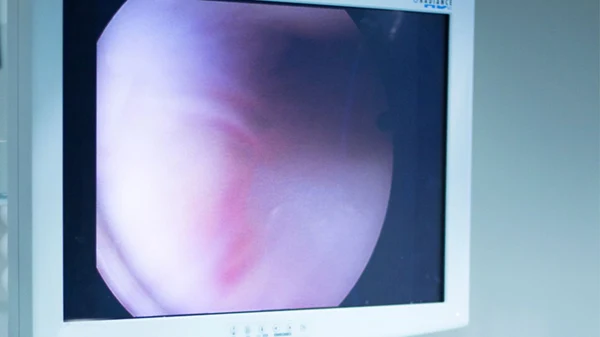

• Surgery involves cutting the tight shoulder capsule to improve movement.